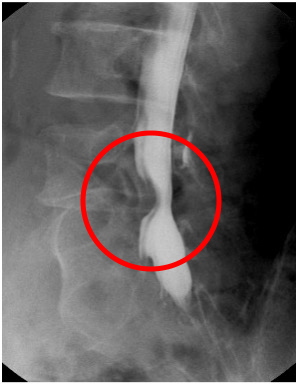

X-TV(X線透視)

椎間板ヘルニアにより

脊髄が圧迫されている

大腸がんにより大腸が

狭くなっている

<どんな検査か(どんなことをするのか)>

X線を常時出すことにより身体の中を透視し、リアルタイムにモニターを見ながら検査・治療を行います。

場合によっては造影剤という薬剤を使用し、より診断精度の高い検査をすることがあります。代表的な検査に胃のバリウム検査があります。

<どんなことが分かるのか>

腰椎ミエロ検査では椎間板ヘルニアの診断。下肢全長撮影によるO脚等の診断。

胃がんや大腸がんの診断。内視鏡を併用しながらの胆嚢・胆道検査・治療等